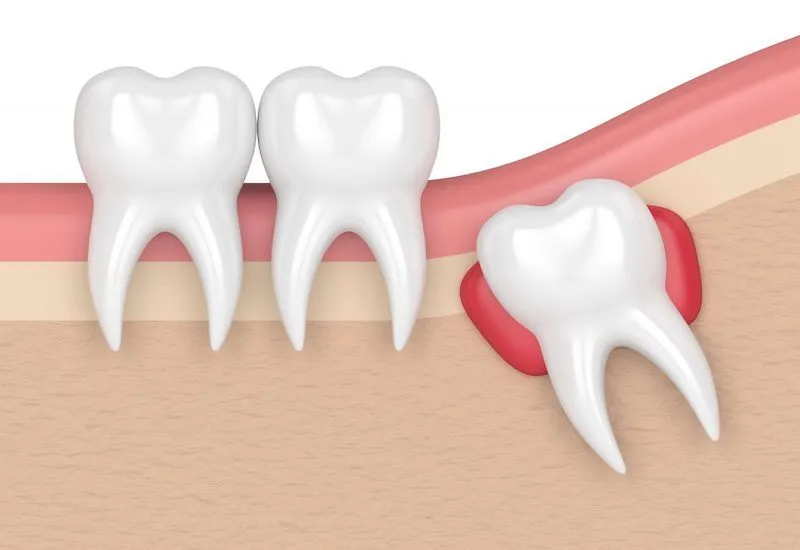

Rất nhiều người băn khoăn về chiếc răng mọc trong cùng hay răng số 8. Những chiếc răng mọc trong cùng này thường chúng ta biết đến